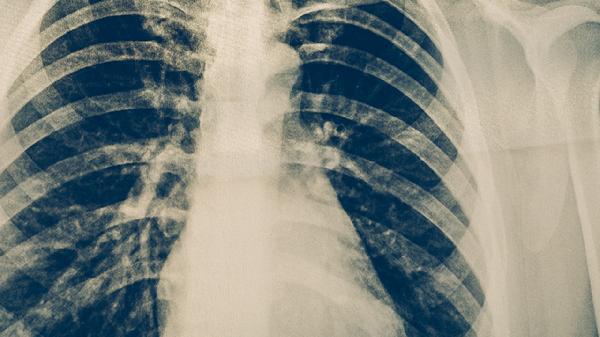

合并胸腔积液或肺不张时恢复延迟。约15%患者会出现中耳炎、皮疹等肺外表现,这些并发症可使炎症吸收时间增加1-2周。重症病例可能遗留肺功能损伤。

康复期间建议摄入高蛋白食物如鱼肉、豆制品,配合维生素C含量丰富的猕猴桃、橙子。每日进行30分钟散步等低强度活动,监测体温和咳嗽变化。若持续低热或咳黄脓痰超过3周,需复查胸片排除其他感染。恢复初期避免前往人群密集场所,规范用药疗程可降低复发风险。